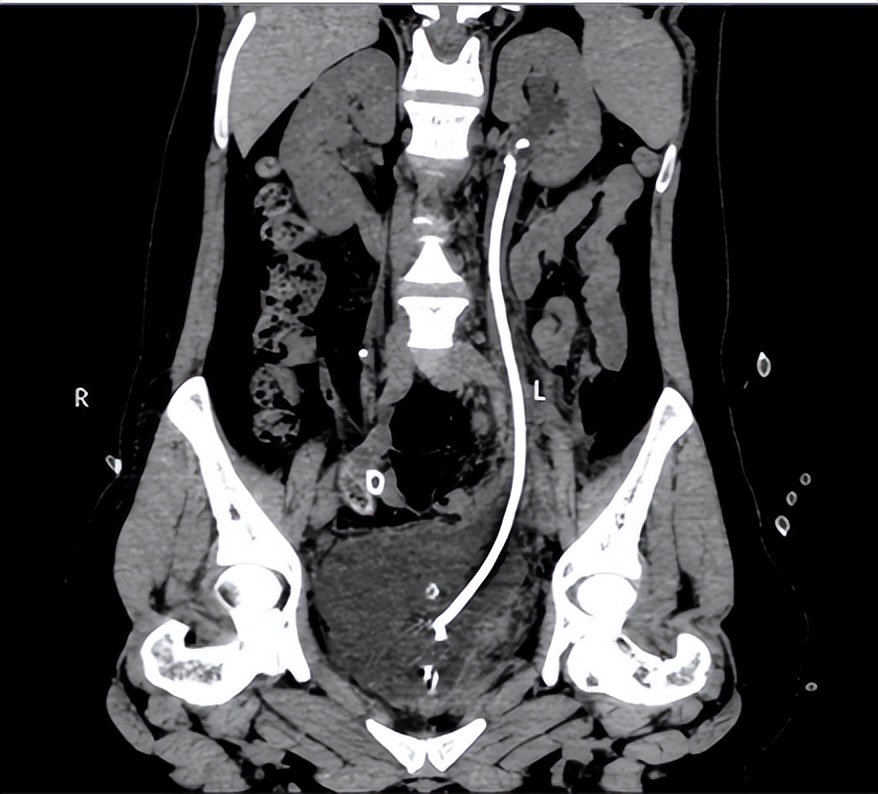

图一 术前泌尿系三维CT 图二 术后3天泌尿系三维CT

在麻醉科和手术室的密切配合下,王春阳教授团队历时4小时,成功用6cm膀胱肌瓣替代了损伤的输尿管、留置输尿管支架完成手术。术中出血量仅20mL,术后连续观察三天没有再发生漏尿情况,患者顺利出院,出院3个月后引流管顺利拔除,仍无漏尿再发,治疗效果受到患者及家属高度认可。